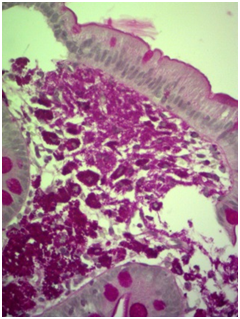

Laboratory tests: Hemoglobin 10mg %, hematocrit 31 %, HIV serology negative. Chest and abdominal CT scans showed bilateral pleural effusions and moderate ascites. Stool search for ova and parasites was negative, and steatocrit was normal. The patient underwent a colonoscopy in which polyps have been found and removed. An upper endoscopy with duodenal biopsies was performed. The histological examination of biopsies showed macrophages with a granular cytoplasma and PAS positive inclusions, compatible with Whipple's disease (Figures 1–4). In the absence of molecular biology test to further confirm the diagnosis, we began treatment with ceftriaxone, with a progressive improvement in the number of bowel movements and the general condition of the patient. After discharge, he continued on sulfamethoxazole and trimethoprim for a year. Medication was discontinued after one year and the patient is asymptomatic.

Figure 1 Macrophages containing bacillus’s PAS positive structures (PAS 400x).

Figure 4 Duodenal mucosa with preserved villous architecture and diffuse infiltrate of macrophages in the lamina propria (HE 400x).